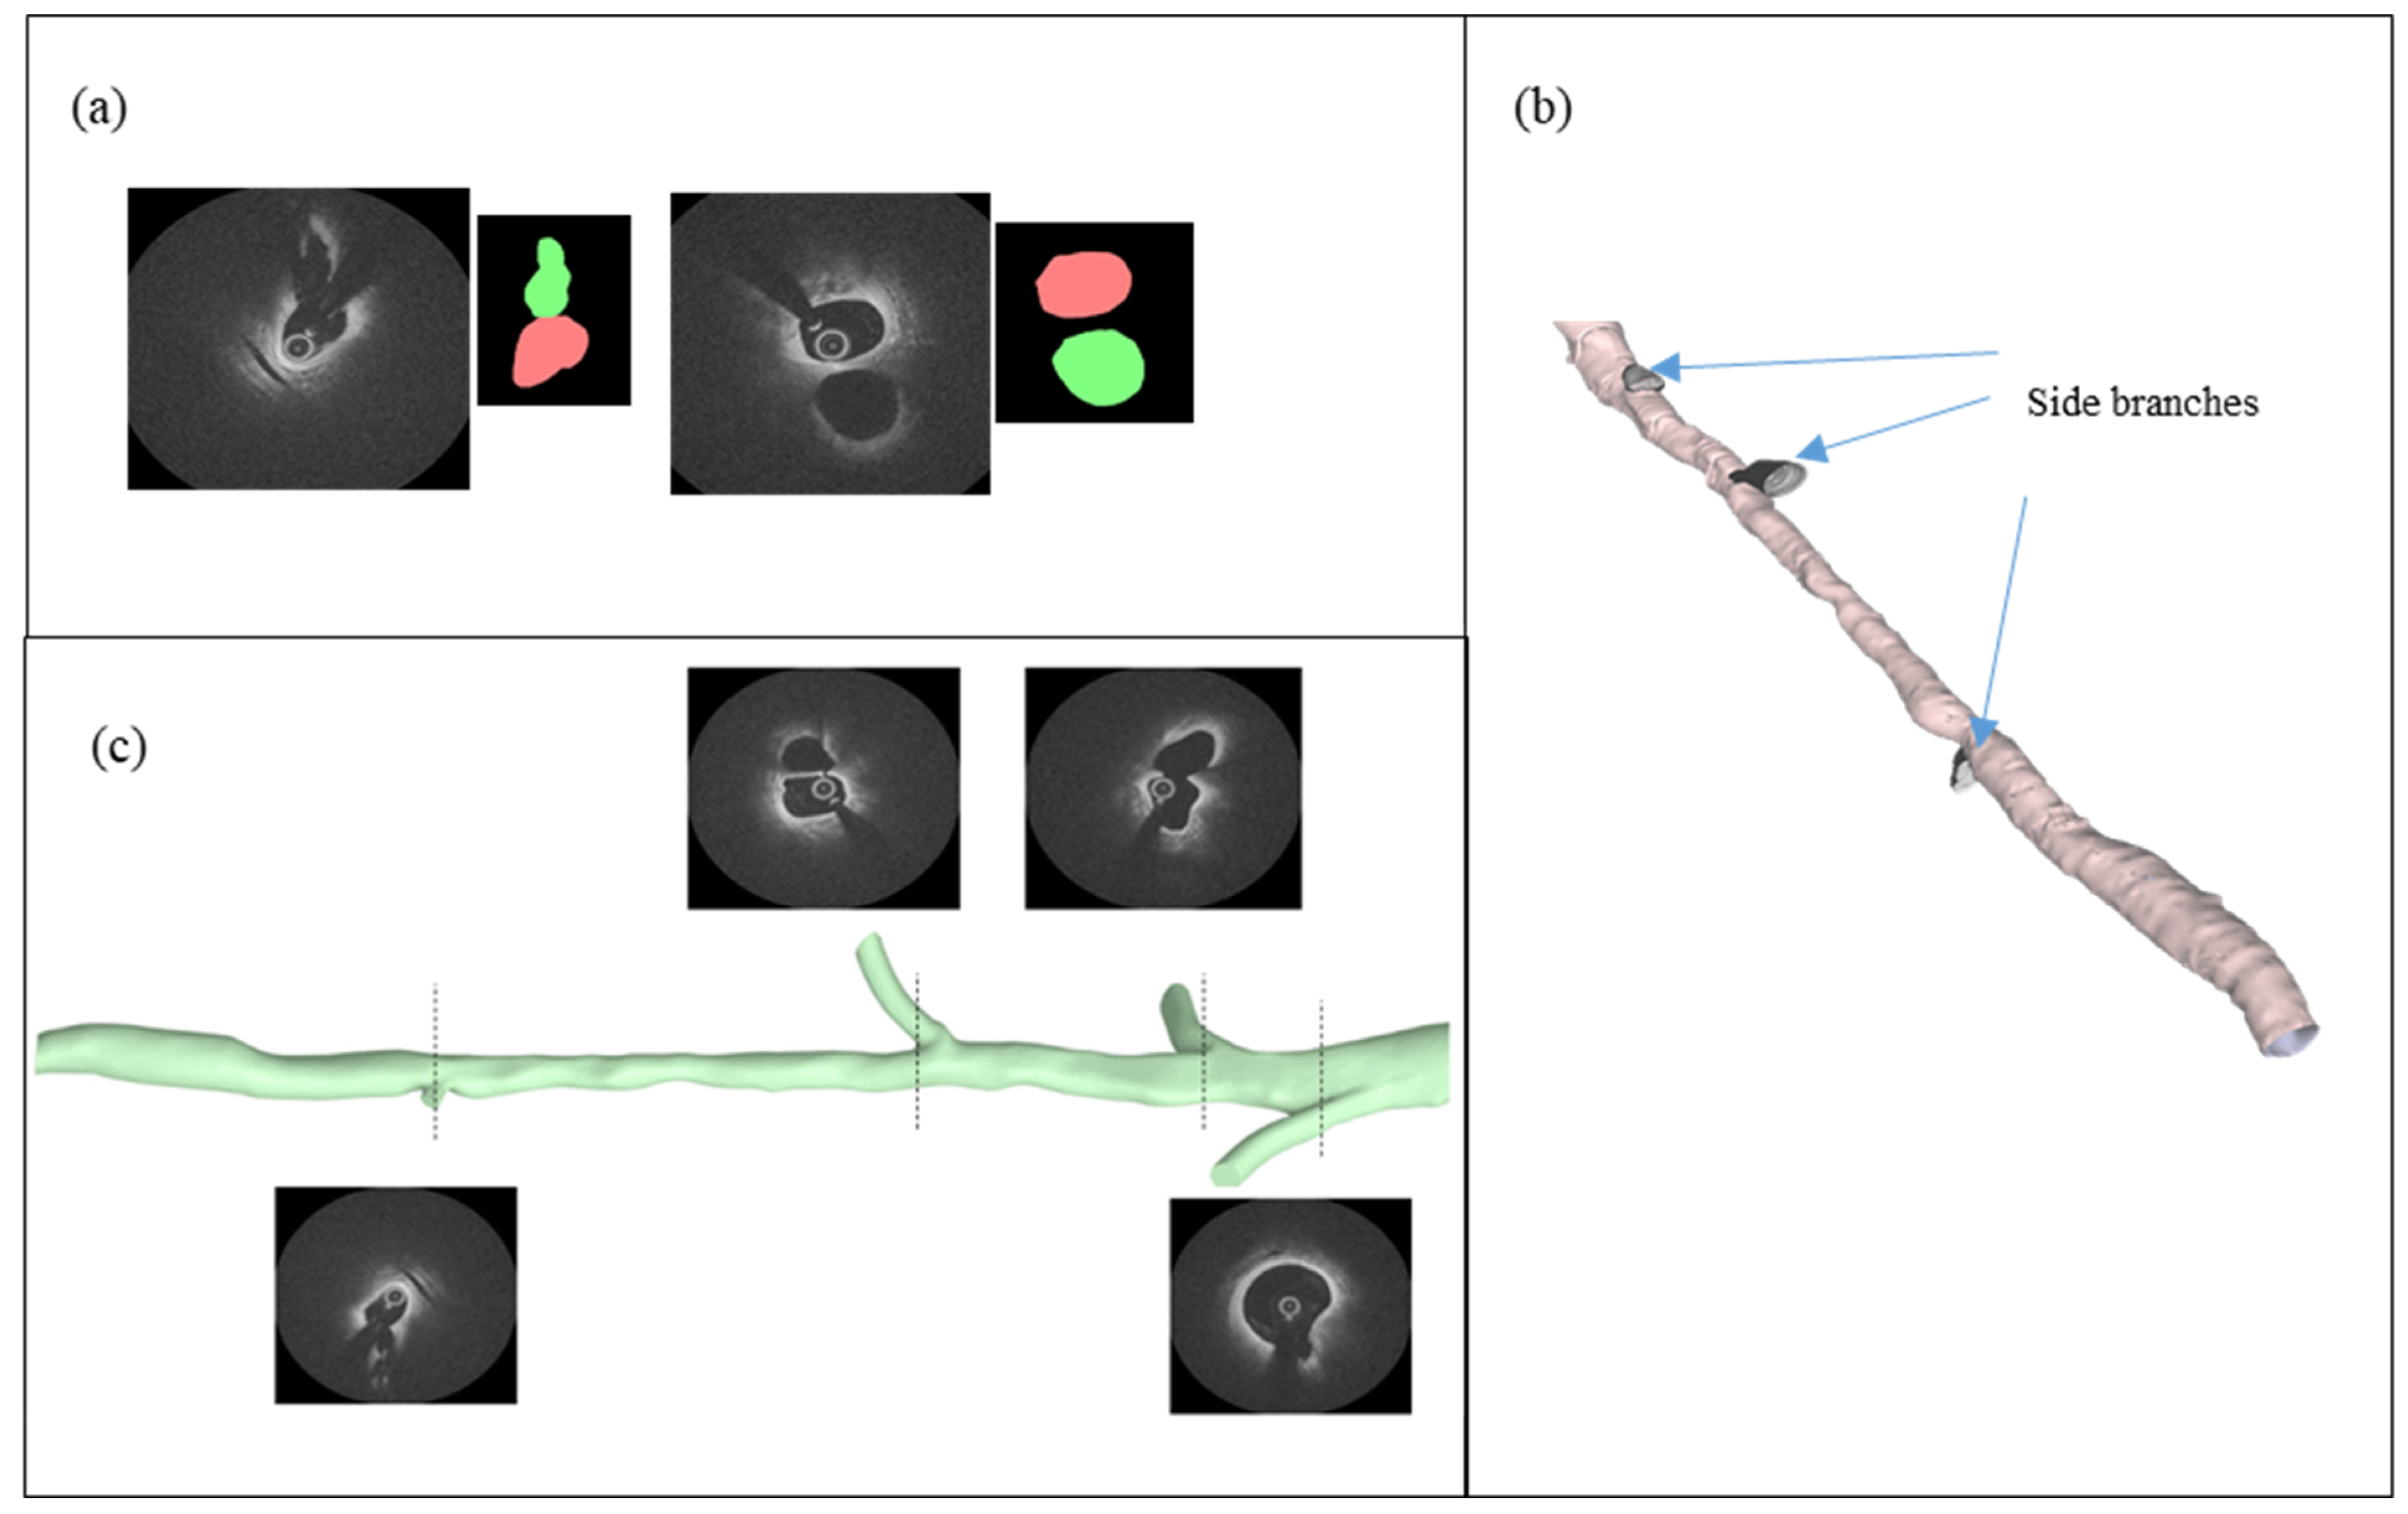

2.2. IVOCT Imaging

2.4. Vessel Segmentation and Reconstruction

3.2. FFR Analysis in OCT-Reconstructed Vessel Models